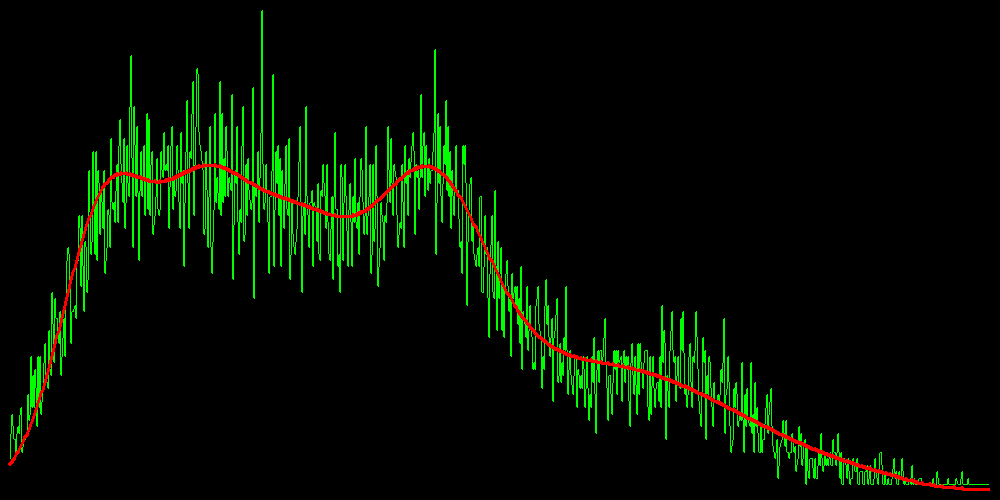

Распределение интенсивностей вокселей в каждом случае является нормальным. Т.е. у нас есть всё необходимое, чтобы, используя EM, найти параметры каждого источника.

Зеленая линия — гистограмма интенсивностей, красная — полученная математическая модель.

Теперь, когда мы знаем параметры каждого источника, мы можем вычислить пороги — значения интенсивностей, при пересечении которых, принадлежность вокселя меняется с одного источника на другой. Нас интересуют:

1. Порог внешней границы сосуда. Если интенсивность вокселя ниже этого значения, то считается, что он вообще не принадлежит сосуду;

2. Порог внутренней границы сосуда. Если интенсивность вокселя больше этого значения, то он

относится к просвету сосуда, т.е. к смеси крови и контрастного вещества;

3. Порог кальция. Если значение интенсивности вокселя больше этого значения, то он относится к кальцию.